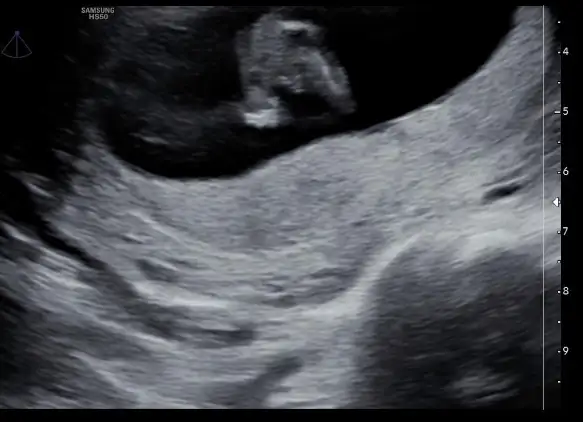

Kızlar merhaba, banada 11 artı 5 te yüzde 80 kız dedi, ama netten bakıyorum daha dıyo üreme organı olusma aşamasında.. Aslında bana farketmez ama insan merak ediyor neden bu kadar erken soyledi ki şüphede kaldık.

Doktorların yanılma payı her zaman var ama daha cinsiyet tomurcukları yeni oluşuyor. 16 17 haftadan önce söylenenlerin tutmama durumu daha yüksek

O yüzden diyorum işte insan ister istemez ona göre birşeyler bakıyor giyim olsun kullanacağı ürünler olsun. Bence bekleyin en güzeli detaylı ultrasonda çıkıyormuş zaten. 20.haftalarda.